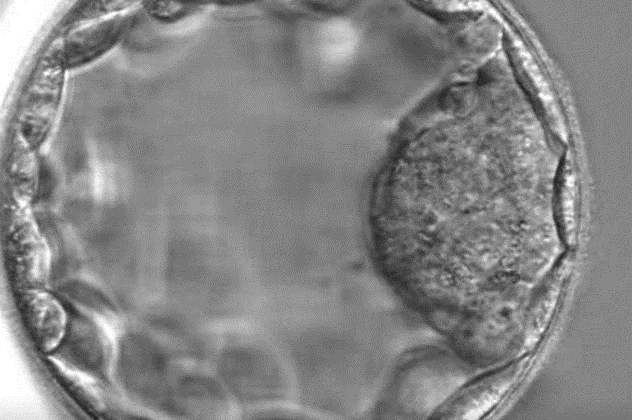

Blastocysta: Pětidenní embryo

Blastocysta je časná fáze vývoje embrya, která vzniká pátý den po oplození. Buňky blastocysty jsou rozděleny na vnitřní vrstvu – embryoblast, ze kterého se později vytváří plod a na vnější obal trofoblast, který dává za vznik placentě.